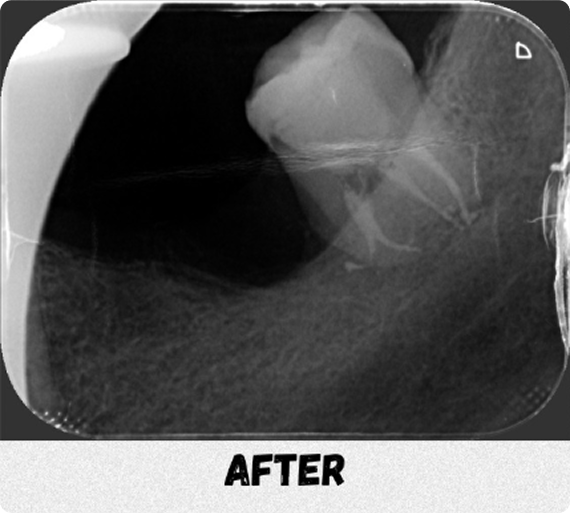

“Instead of extraction, I chose root canal therapy because it’s the only molar he has left on this side to chew.”- Dr Karen